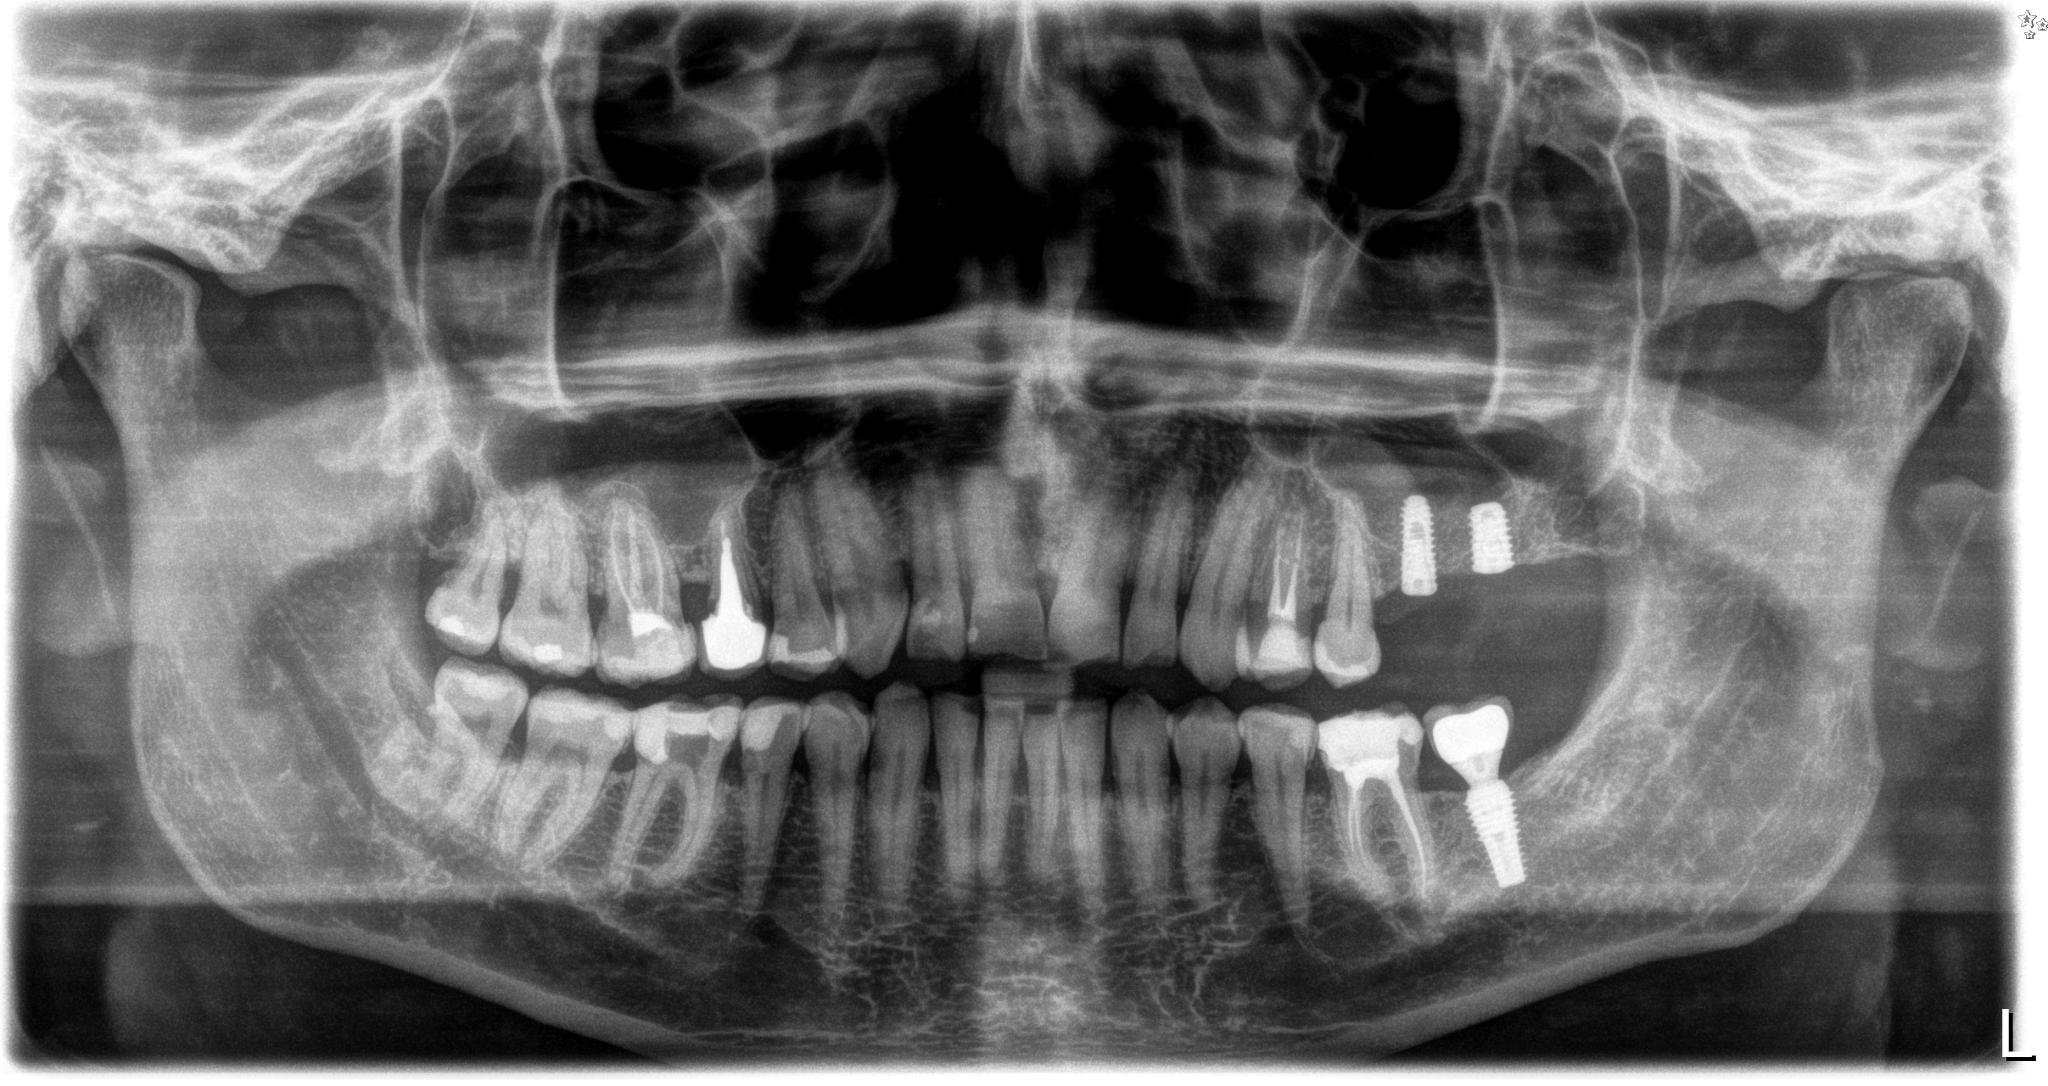

Podczas wizyty u chirurga stomatologa, analizujemy potrzeby pacjenta i wykluczamy ewentualne przeciwwskazania do zabiegu. Podczas pierwszej wizyty robimy zdjęcie pantomograficzne.

Każdego pacjenta poddajemy badaniom lekarskim. Niektóre choroby są bowiem przeciwskazaniem do zabiegu wszczepienia implantów. Informują one nas o stanie kości i pozwalają na bardzo dokładne zaplanowanie leczenia implantologicznego.

Zdjęcie RTG pacjentki przed implantacją oraz po wszczepieniu 2 implantów.